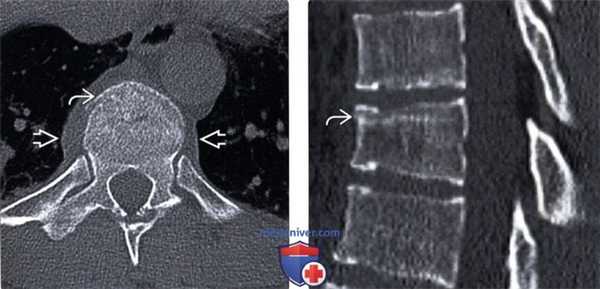

(Слева) КТ, аксиальный срез: компрессионный перелом в области переднего отдела тела позвонка. Дополнительным признаком перелома служит гематома паравертебральных тканей. Для дифференциальной диагностики компрессионных и взрывных переломов эффективны сагиттальные изображения.

(Справа) КТ, сагиттальный срез: компрессионный перелом тела позвонка с минимальным снижением высоты тела. Плотная полоса в толще тела позвонка представляет собой зону импакции трабекулярной кости.